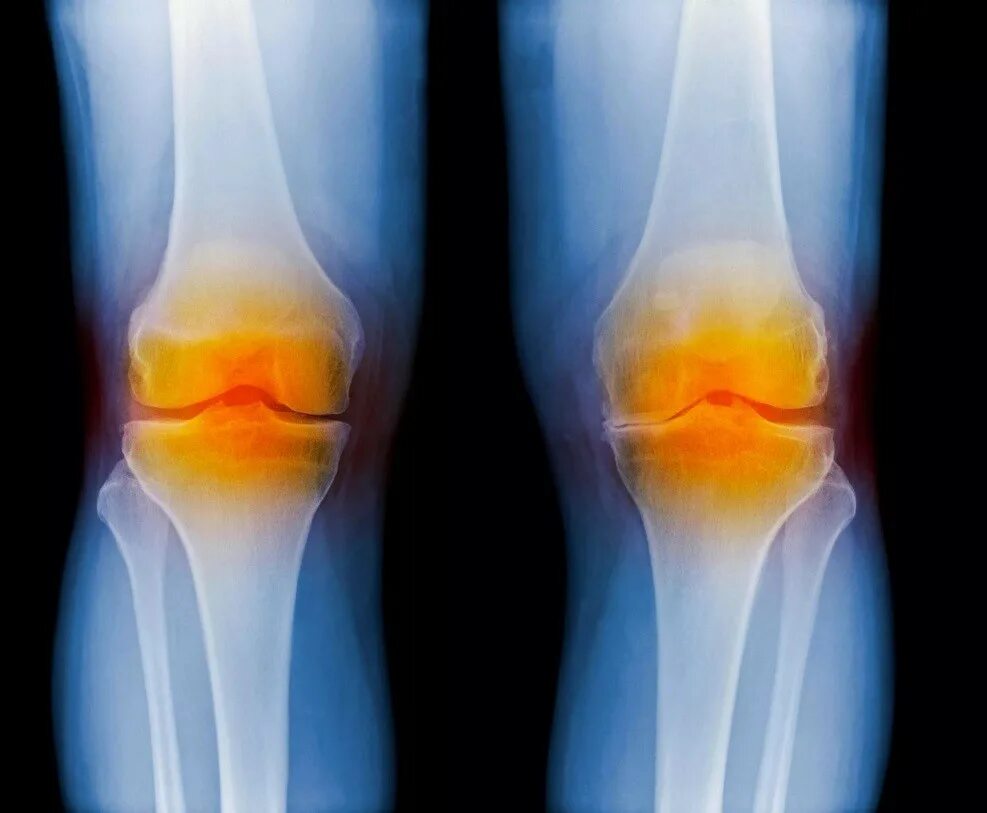

Явления остеоартроза